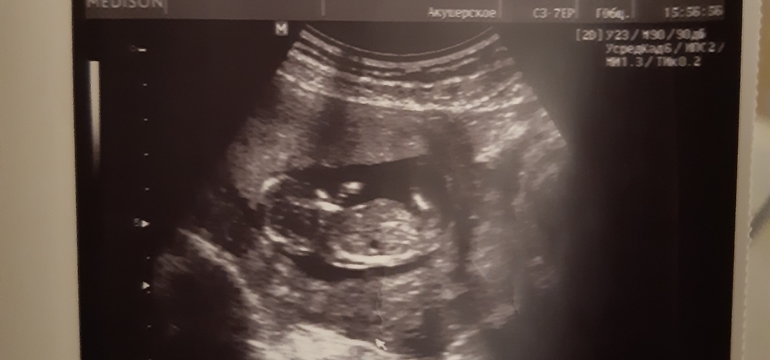

Мне кажется, что то, что вы сейчас обвели - копчик) тк ребёнок спиной лежит)))

Твой больше спинкой повернут, только вот ножка правая или левая видна?)

Совсем нет ракурса тут. Крупным планом голова и живот. Промежность смотрят в другом ракурсе. Так рано огромная погрешность. Мне в 17 недель правильно сказали. В 20 на скрининге подтвердили

Совершено не верный ракурс. Тут не видно полового бугорка😊

Он лежит больше спиной к нам. То что вы обвели может быть и мальчиком и девочкой. Надо строго по наклону смотеть. А тут как бы с попы.